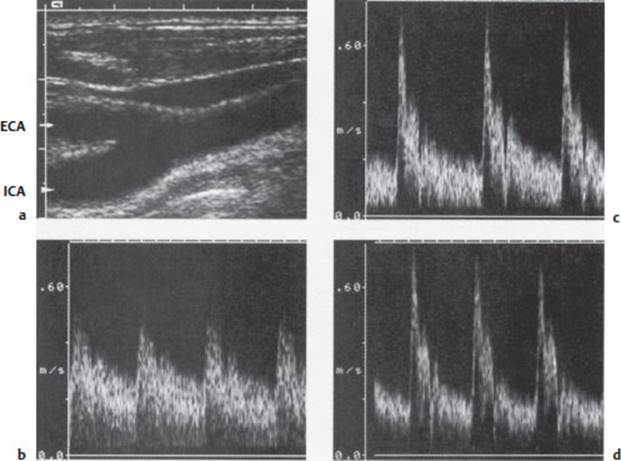

The Doppler signal can be represented graphically as a frequency spectrum that changes over time (Fig. 4.25). It can also be transduced into an audible signal. Ultrasound waves are reflected to varying extents by different types of tissue with different acoustic resistance; thus, the profile of reflected echo intensities can be used to construct a two-dimensional sectional image of the insonated tissue. The so-called B image (“brightness mode”) or echotomogramis a grayscale representation of the tissue (Fig. 4.25a). The combination of Doppler flow measurement with B imaging is called duplex ultrasonography. The velocity of blood flow can be color-coded and displayed as an overlay on the B image; this is called color duplex ultrasonography (Fig. 4.26).

Fig. 4.25 Doppler study of a normal carotid bifurcation. a Two-dimensional sectional image (B image) of the carotid bifurcation. b–c Doppler frequency-time spectra in the common carotid (b), internal carotid (c), and external carotid arteries (d).